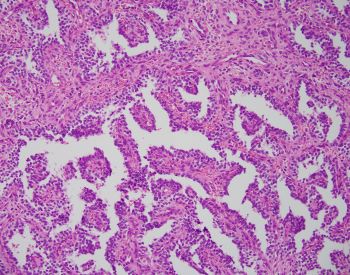

Sections show large polypoid, densely cellular fragments of endometrial stroma composed of bland cells that are small and uniform, resembling proliferative-type endometrial stroma. Admixed within this stroma are sex cord-like elements, arranged in cords, trabeculae, and retiform patterns. Endometrial stromal nodules are rare tumors. They can display a number of different histologic variants, including sex cord-like elements (as in this case), smooth muscle, endometrioid glandular elements, and myxoid/fibroblastic. A characteristic network of arterioles around which neoplastic cells often whorl is distinctive as well. A diagnosis of an endometrial stromal nodule can only be definitively made after ensuring there is no myometrial or lymphovascular invasion, and often this requires a resection rather than just a biopsy. This brings up an important differential: low-grade endometrial stromal sarcoma, as invasion renders the diagnosis of sarcoma. So, it is best to defer a definitive diagnosis to a resection specimen. Both nodules and sarcomas have similar histologic features, including sex cord-like elements. Both are also characterized by a t(7;17)(p15;q21) translocation resulting in JAZF1-SUZ12 fusion (there are others, but this is the most common).

Uterine tumor resembling ovarian sex cord tumor is also in consideration. However, the presence of endometrial stroma excludes this diagnosis. An endometrial polyp could come under the differential here as well, given the large polypoid fragments and larger, thick-walled blood vessels. The important diagnostic feature lacking in this case for a polyp are branched or cystically dilated endometrial glands within an altered, fibrotic stroma. The presence of sex cord-like elements really excludes the possibility of a cellular leiomyoma, but stromal tumors and uterine smooth muscle tumors (ie leiomyomas) can have overlap. Features favoring a cellular leiomyoma include prominent thick-walled blood vessels and cleft-like spaces.